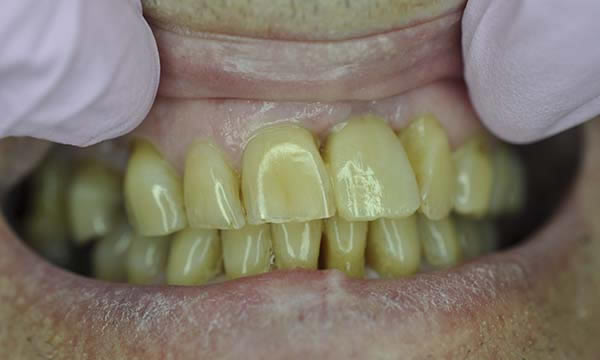

Case G

A failed apicectomy in the UL1 was diagnosed after a history of labial draining discharge and mobility. The patient was referred to us for treatment and a diagnostic wax up was used to discuss the proposed finished crown, estimated gingival margin position and crown height with the patient.

A tooth bourn position guide allowed for predictable implant placement within the aesthetic zone. Collaboration with with Smile Dental Laboratory and clinical pictures helped to produce a great shade match and natural looking result.

Before Treatment

During Treatment